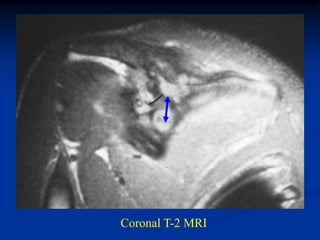

Case #431

20 year male with EG scapula

CT scan

Coronal T-2 MRI

Axial T-2 MRI